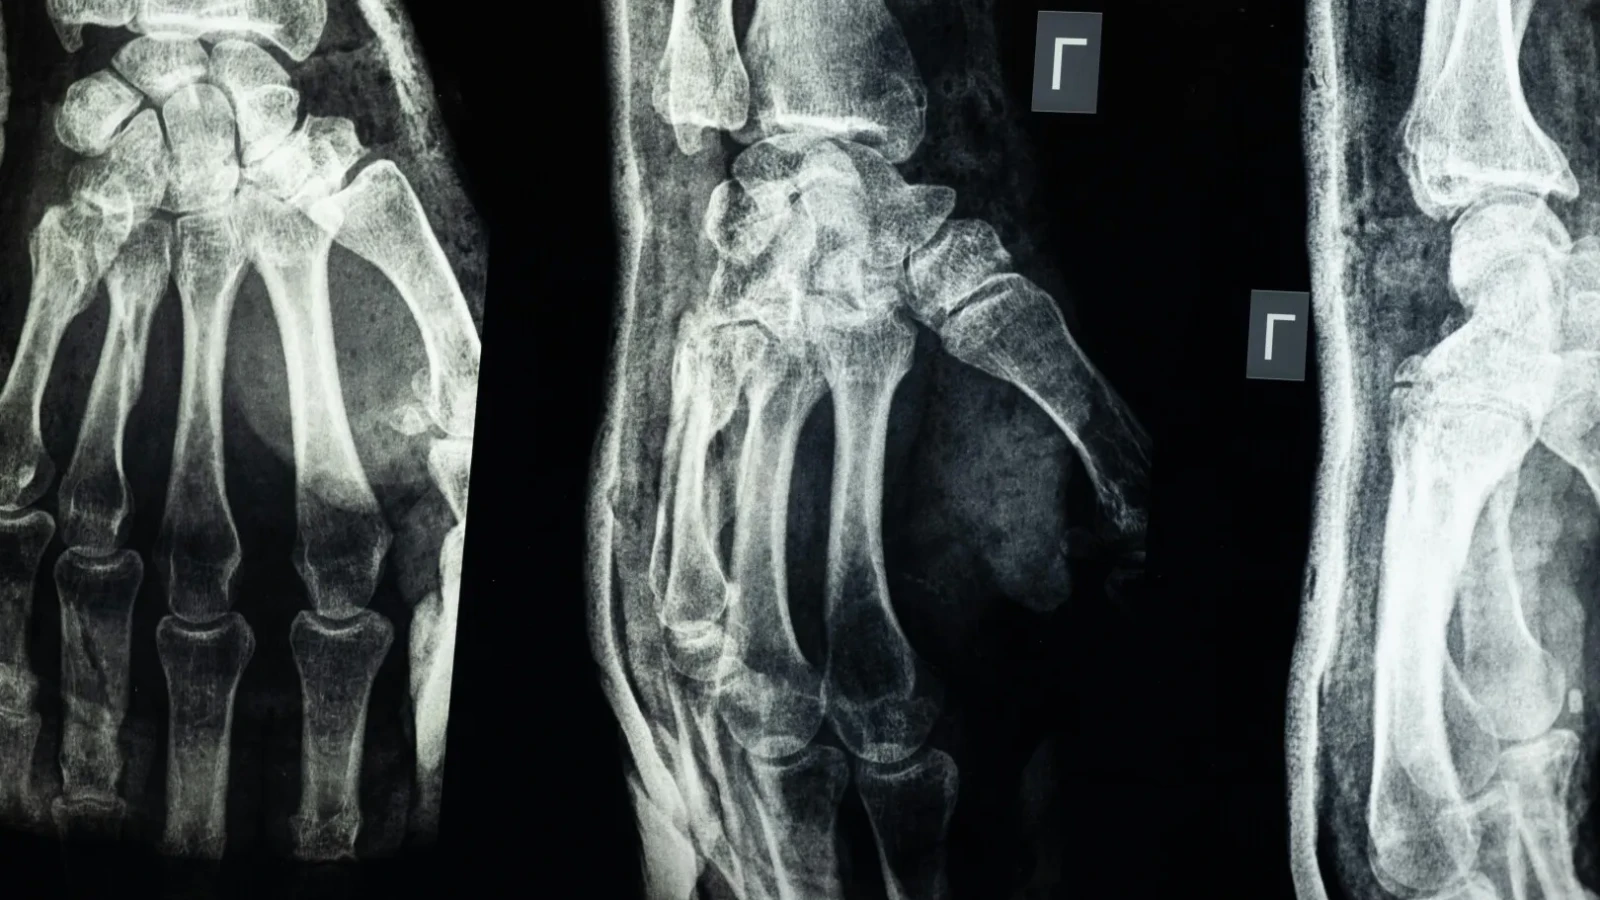

O echipă de cercetători din provincia Zhejiang, China, a dezvoltat un nou tip de adeziv medical capabil să „sudeze” oasele fracturate în numai 2–3 minute. Produsul denumit „Bone-02” ar putea înlocui în viitor implanturile metalice folosite în ortopedie și ar reduce semnificativ timpul de recuperare al pacienților.

Testele de laborator și studiile clinice pe peste 150 de pacienți au arătat că „Bone-02” oferă o rezistență comparabilă cu cea a implanturilor metalice, având o forță de lipire de peste 400 de livre și o rezistență la compresiune de circa 10 MPa.